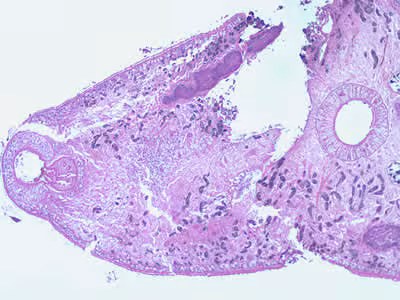

A patient complaining of intermittent symptoms including coughing up blood, fever, and other vague “flu-like” symptoms saw a physician. The patient reported working at a sushi restaurant and eating a raw crab on a dare (Figure A shows a crab similar to the one that the patient ate). Blood tests were ordered and results included peripheral eosinophilia of 10% and a history of bilateral pneumothorax (free air or gas in the pleural cavity). A biopsy yielded a cyst containing a structure 5 mm in length and 2 mm in width. Figure B (40×) and Figure C (100×) show a hematoxylin and eosin (H & E) stained section of the specimen. Figure D (400×) shows an object which measured 80-90 µm by 40-45 µm. Similar objects were found in low numbers in sections of lung tissue. What is your diagnosis? Based on what criteria?

Figure B